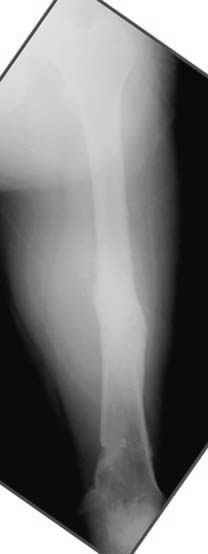

Несколько снимков из моей коллекции, чтобы разьяснить, почему мы до сих пор делаем различные варианты остеотомии.

На рисунке N1 предоперационный план лечения ложного сустава шейки бедра- линия ложного сустава, угол и направление введения импланта, клиновидная остеотомия в градусах и миллиметрах, второй снимок после коррекции, расчет, на сколько удлиняется конечность и размеры импланта;

N3 рисунок окончательный снимок, после операции моя рентгенограмма должен выглядеть примерно как эта картина. На N4 снимке клин перед удалением; N5 послеоперации 3 нед.; N6 окончательная рентгенограмма.

пластическая модель; и коррекция бедра аппаратом Илизарова.

Узкий к-м канал - тонкий гвоздь- усталостный перелом дистальных винтов - развитие нестабильности и как ее результат остеолиз вокруг гвоздя - деформация анатомической оси бедра. Похоже, что я понял почему аппарат, а не новый гвоздь:-)